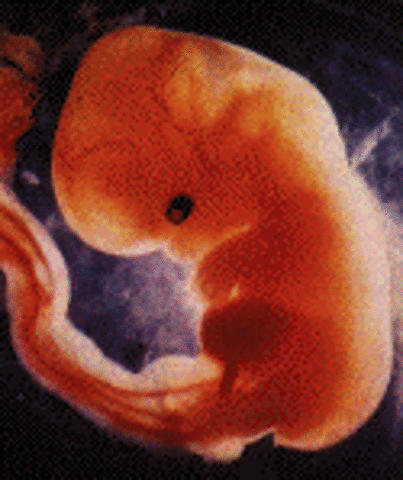

1. The embryo grows to the size of a pin head. 2.• The embryo starts receiving oxygen and nutrition through the placenta 3.the embryo produces hormones which stop the mother's menstrual cycle

1.The first blood cells and blood vessels are developing

2.heart is formed and begins to beat

3.At this time the embryo is still smaller than the size of a raisin

4.The spine and spinal cord grows faster than the rest of the body at this stage and will give the appearance of a tail